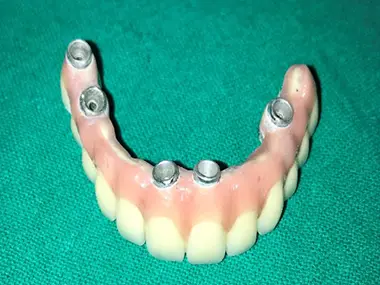

Post TreatmentCase 2: Maxillary cast partial denture & Mandibular

Tooth supported overdenture - ceka

attachment